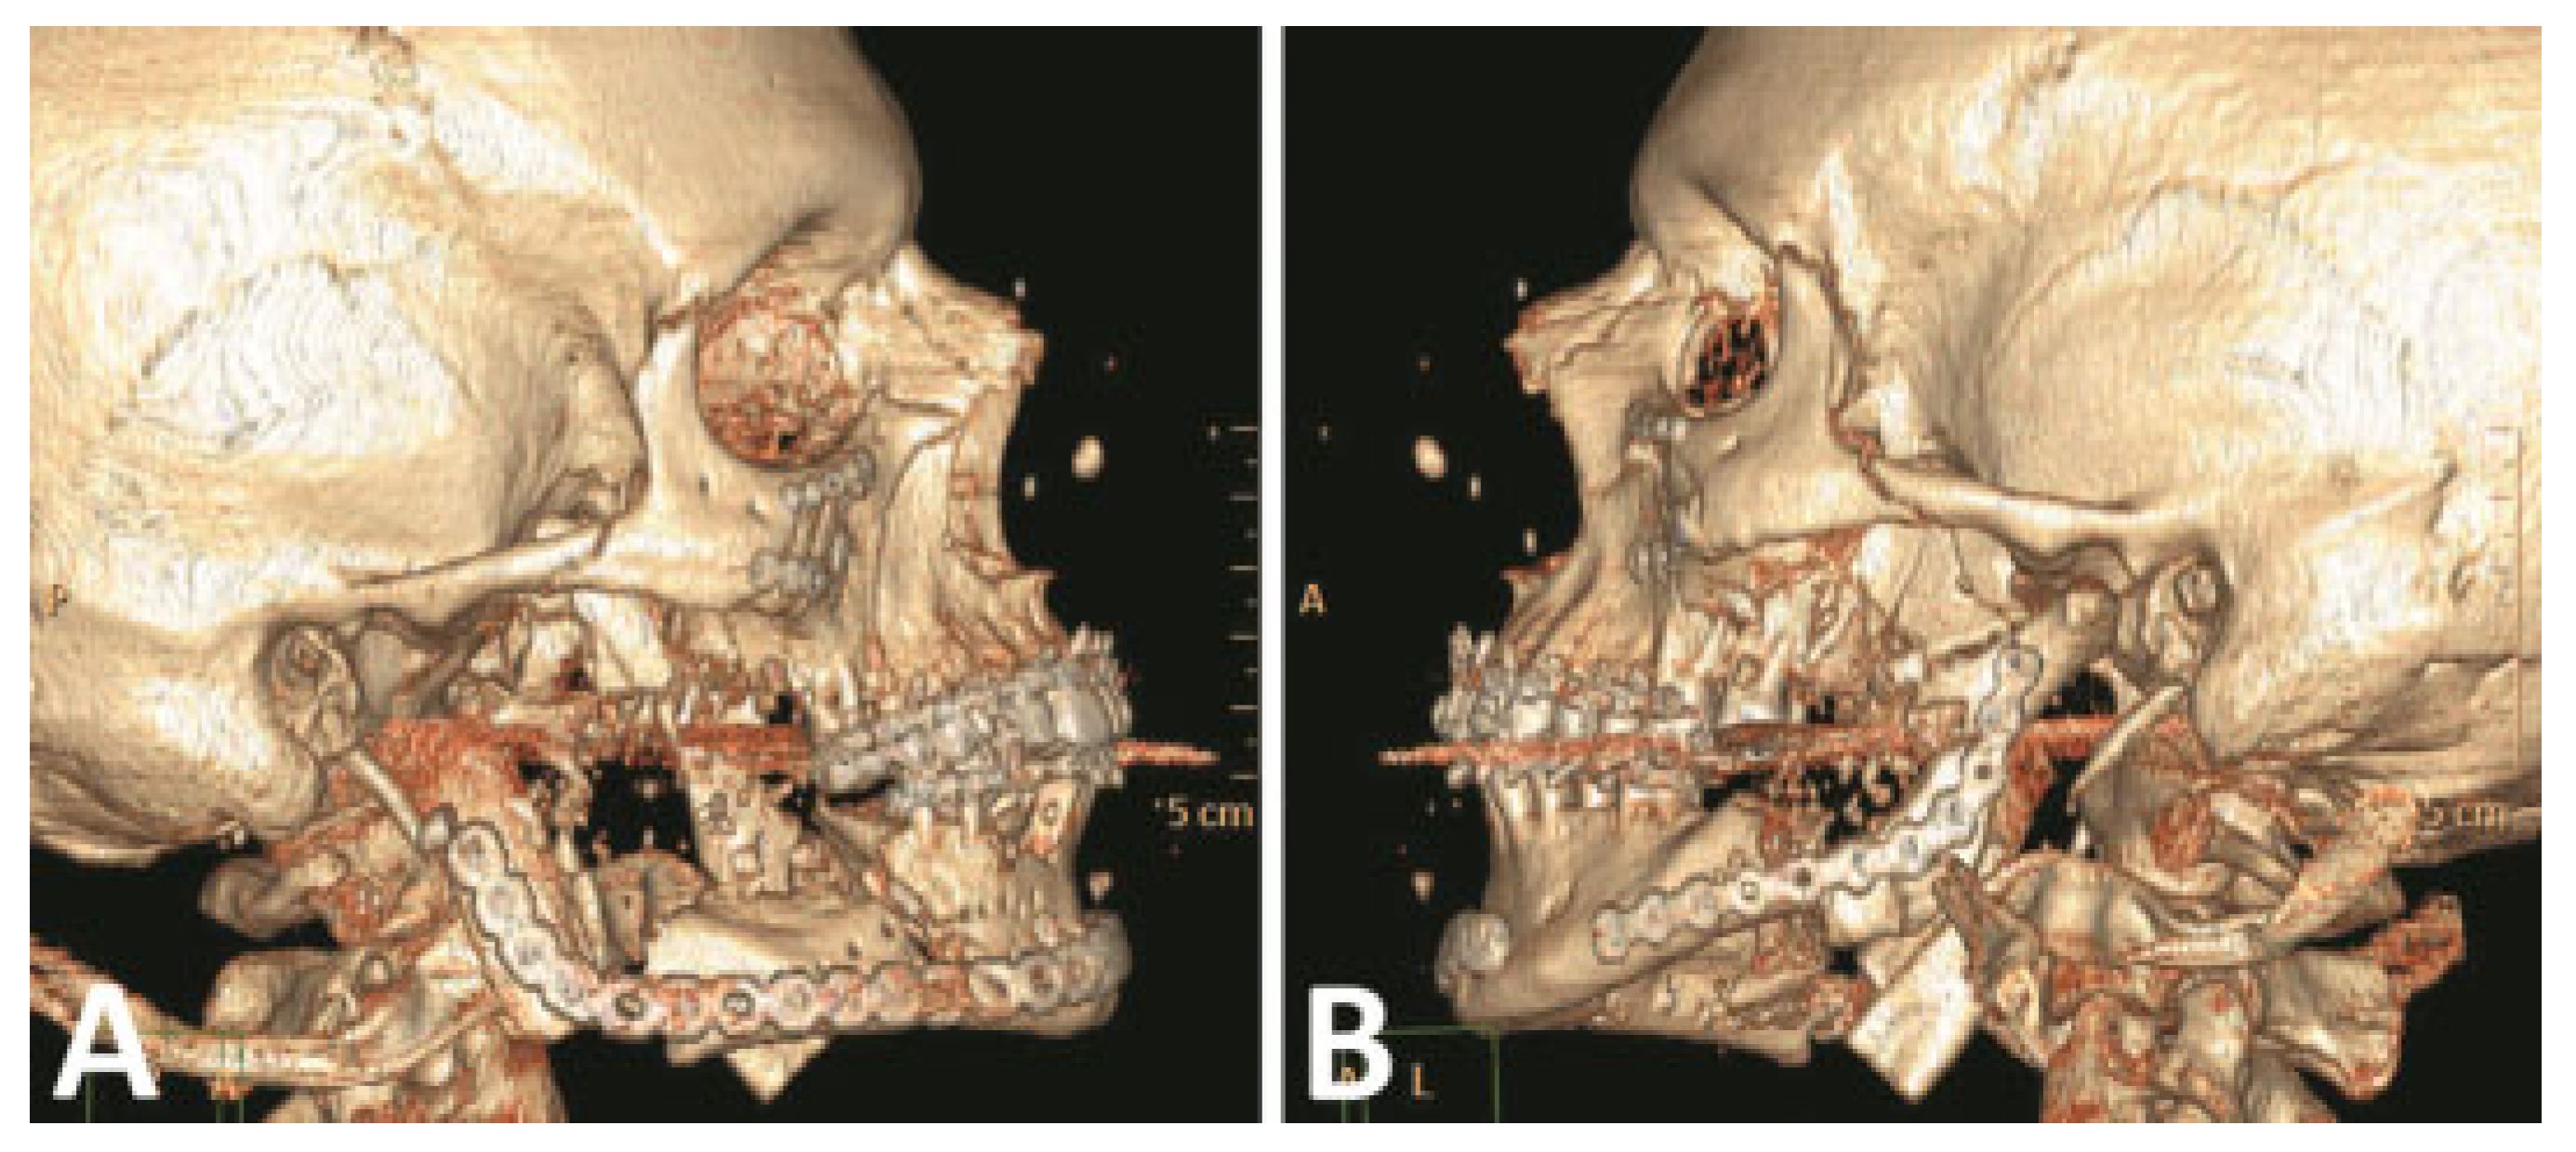

The comminuted left condyle and body fractures were re- paired with 2.0-mm reconstruction plates (Figure 5). A right cheek wound was closed in layers after debridement and placement of a drain.

Figure 5.

(A,B) Primary fracture reconstruction; comminuted right condyle debridement and reconstructed with immediate costochondral graft. (Images are courtesy of Colonel Robert Hale.).

Four weeks after bone reconstruction (Figure 6A), the ear, nose, and throat service performed soft tissue reconstruction of the lip defects with lateral sliding cheek and rhomboid flaps. The postoperative course was complicated by dehiscence of the flap and contracture of the right commissure with failure to achieve lip competence. A revision procedure was performed 6 weeks later with a buccal advancement flap. Nine months after the cheek and mucosal flap reconstructions, the patient presented to OMS service with left mandible pain and swelling, multiple scar contractures, microstomia, and an obvious lip deformity (Figure 6B). Evaluation showed hardware failure with nonunion of the left mandible body and a continuity defect of the right mandible body. To improve his immediate concern of excessive mucosa display, the upper right lip scar was excised and recon- structed with a full-thickness skin graft harvested from the left chest.

Figure 6.

(A) Perioral deformity after skeletal repair. (B) Resultant deformity after bilateral cheek advancement flaps and reconstructive advancement of lower lip and a buccal mucosa advancement flap to reconstruct maxillary lip. (C) Incision markings for bilateral cervico- facial advancement/rotational flaps. (D) After cervicofacial flaps and anteriorly based ventral tongue flap to reconstruct lower lip. (Images are courtesy of Colonel Robert Hale.).

Two months later patient 2 was taken back to the operating room by OMS service for mandible and lower lip reconstruction. After tracheotomy, a midlevel cervical flap was developed to expose the mandibular body. Previously placed hardware was removed and 2.4-mm reconstruction plates placed. The area was treated with recombinant human bone morphogenetic protein-2 with titanium mesh to maintain space for bone regeneration. A procedure was created for this patient to lengthen the lower lip, increase the intercommissure distance, and reconstruct the missing lower lip vermillion: The lower lip, chin, and neck were divided vertically at the midline to the level of the cervical incision and cervicofacial flaps developed (Figure 6C). These cervicofacial flaps were then advanced and rotated anterosuperiorly to increase the lower lip height and intercommissure dimension. An anteriorly based ventral tongue flap was then used to reconstruct the lower lip vermilion (Figure 6D).

Postoperatively, the patient was heavily sedated for 2 weeks with a mouth prop between his teeth to avoid trauma to the tongue flap. The tongue pedicle was divided 18 days postoperatively. As a result of the surgery, the patient displayed facial features representative of upper and lower lips. The lips were adequate when viewed frontally but on profile, the lower lip projected poorly. In addition, lip incompetence persisted.